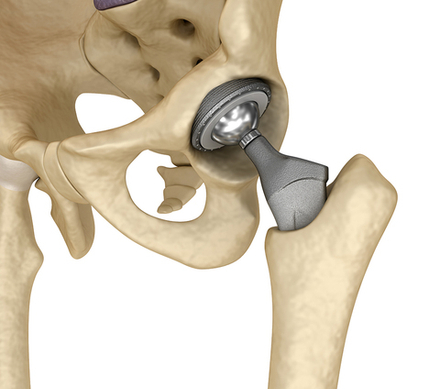

Специализация:

• хирургия тазобедренного и коленного суставов

• эндопротезирование

• артроскопические и реконструктивные операции